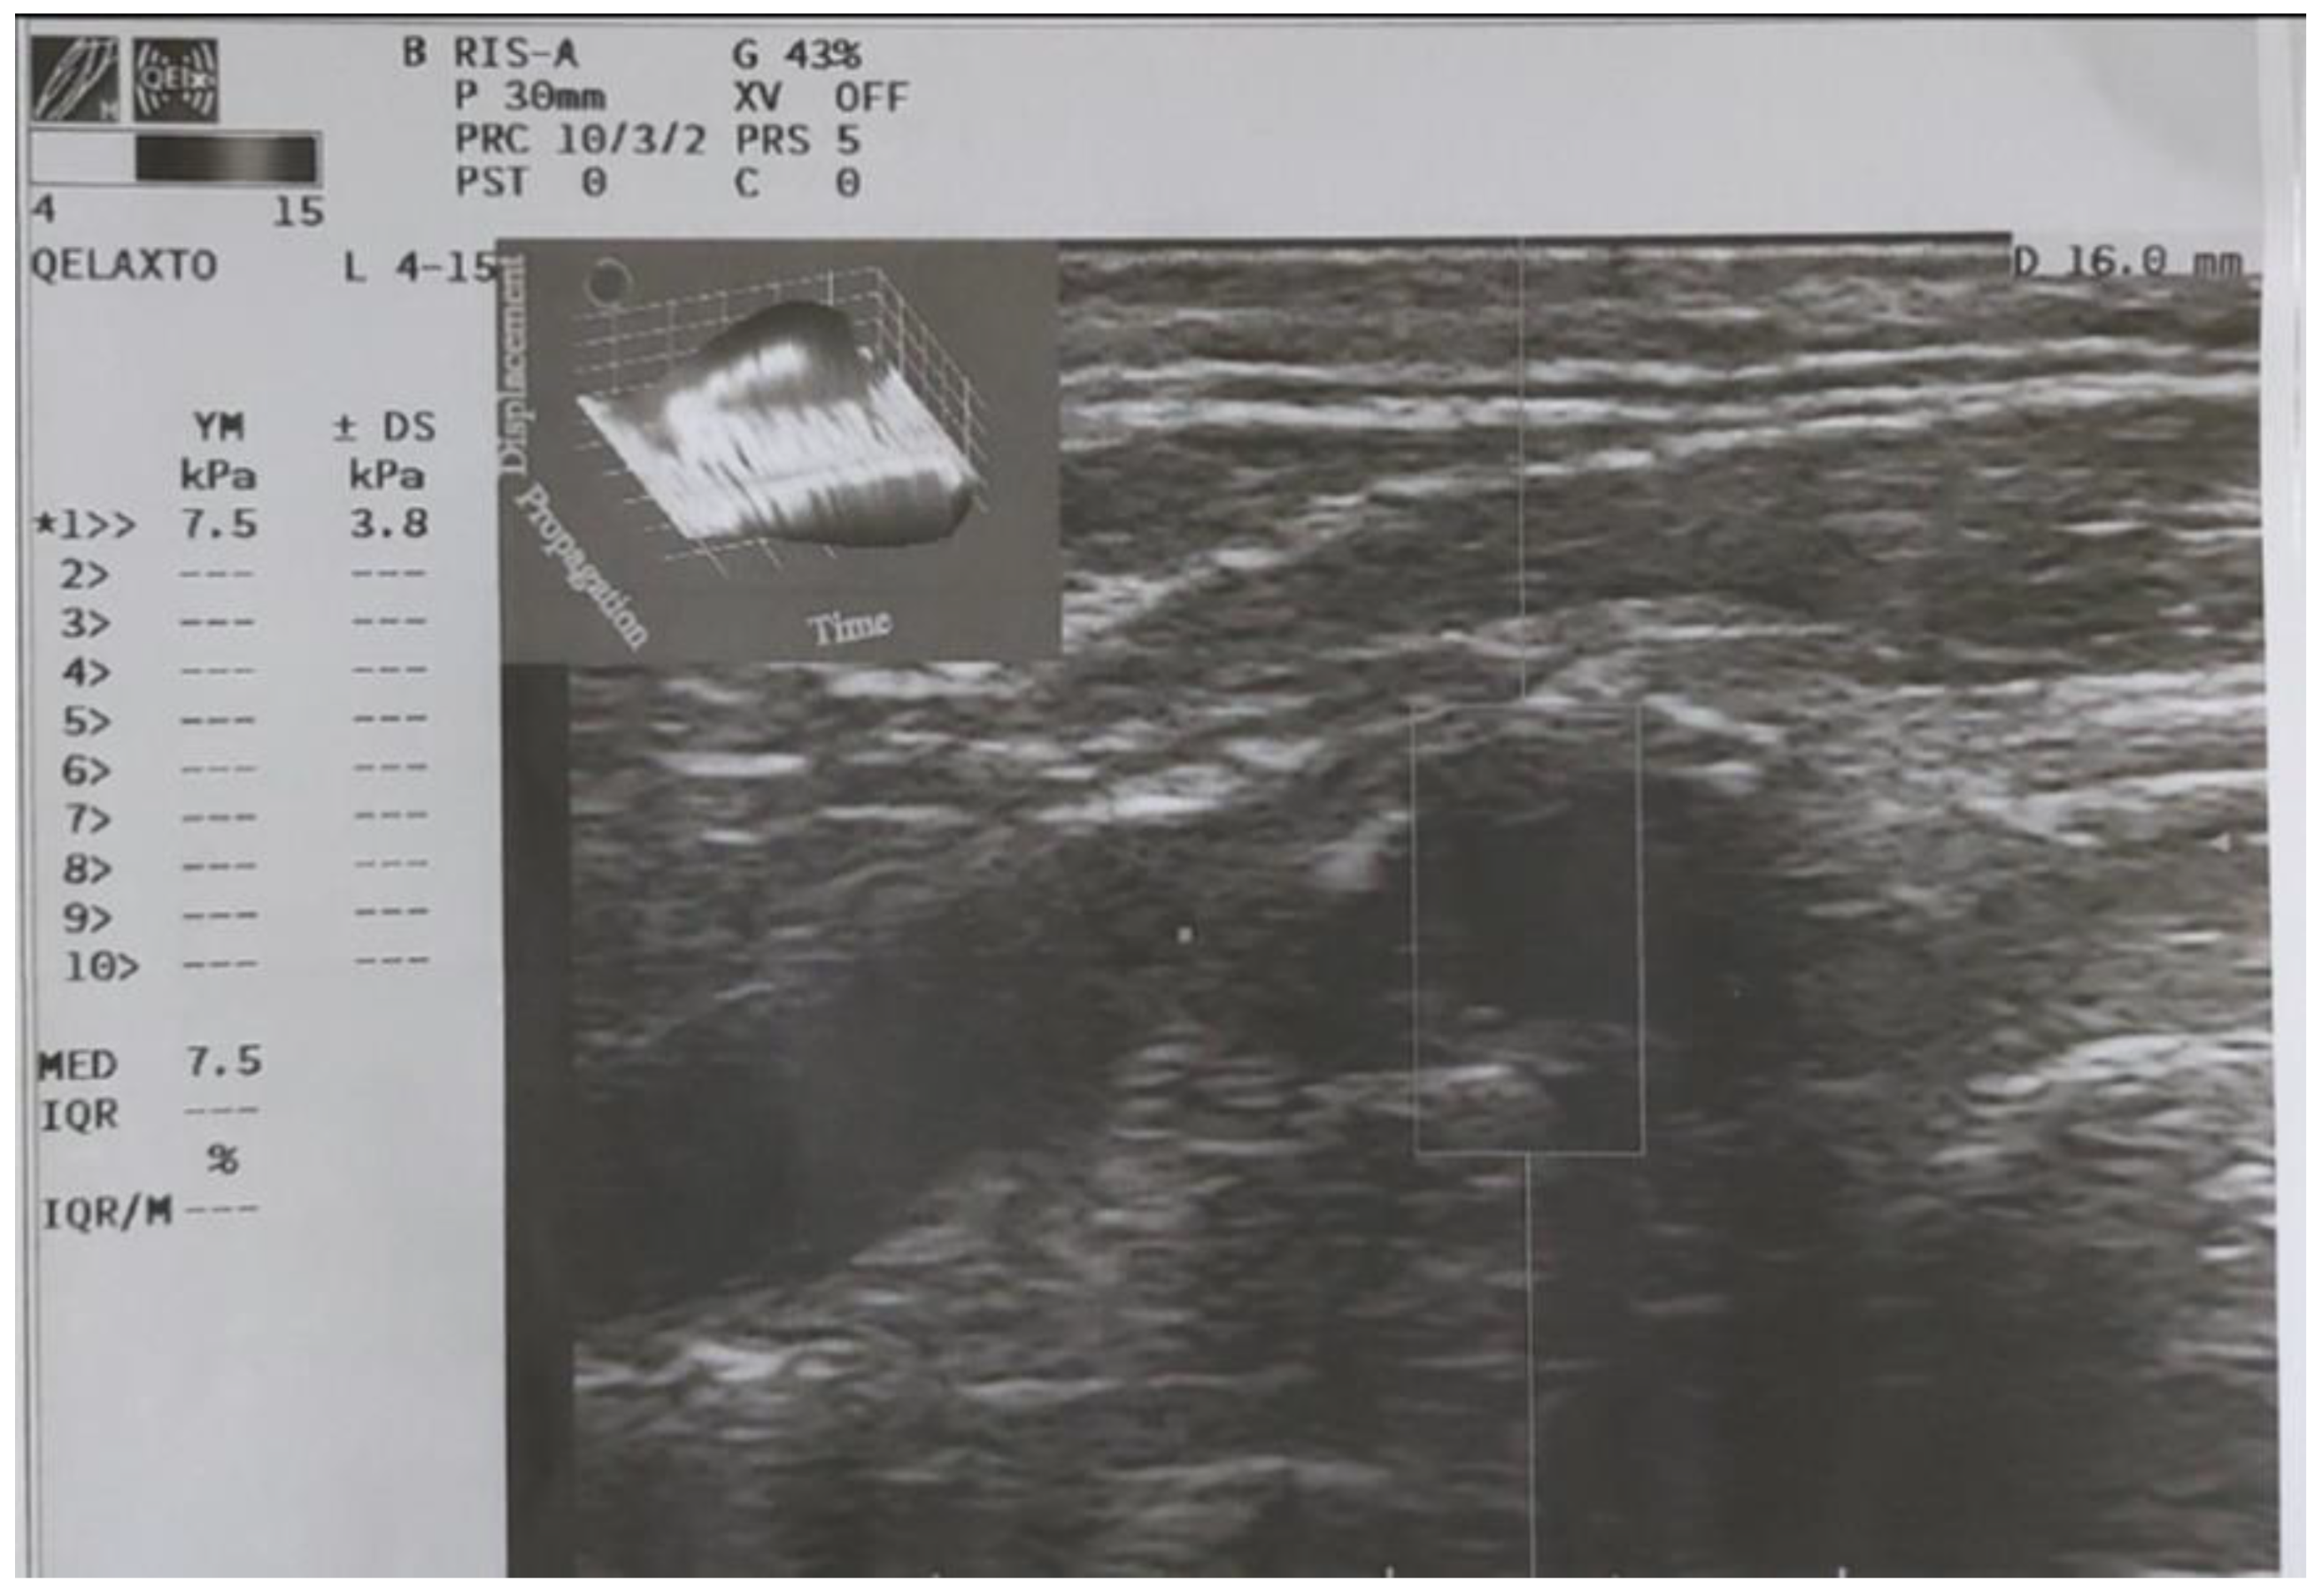

The Q-Elaxto evaluation was performed with the patient in the same position as for QAS. The linear probe was placed along the longitudinal axis on the side of the carotid stenosis to evaluate quantitatively the stiffness of the carotid plaque, in terms of Young’s modulus (Figure 4).

Figure 4.

Q-Elaxto evaluation of the carotid plaque with measurement of Young’s Modulus.